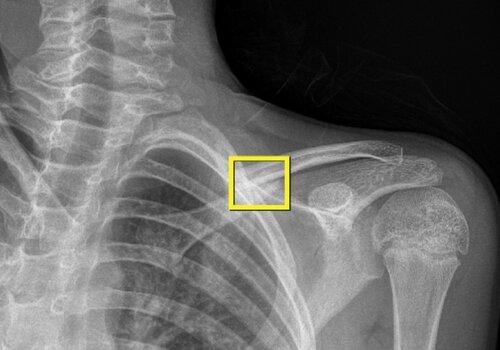

L’IA occupe une place grandissante dans l’analyse des images en détectant des lésions (fracture, tumeur…) ou en effectuant des comparaisons d’un examen à l’autre (suivi en oncologie). Plus surprenant, l’IA peut faire des diagnostics qui échappent totalement à l’œil du radiologue ! L’IA permet aussi de traiter les images avant qu’elles ne soient vues (en IRM par exemple). Enfin l’IA peut être utile en aidant le prescripteur à choisir le bon examen d’imagerie ou en l’alertant d’une urgence thérapeutique.